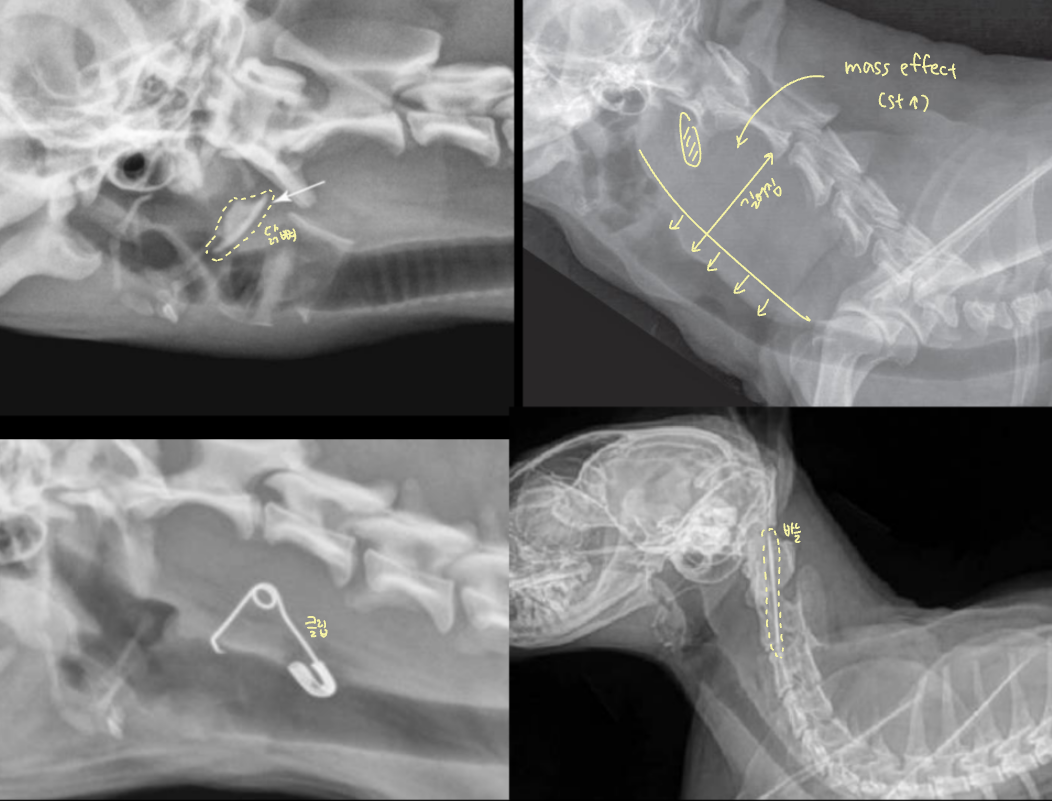

Tracheal Collapse (TC, ๊ธฐ๊ด ํํ)

| Tracheal collapse | |

|---|---|

| ์์ธ : ์ฃผ๋ก ์ฐ๊ณจ์ฐํ์ฆ(chondromalacia) ์ฆ์ : Goose-honking sound (grade 3 ์ด์์์) ์น๋ฃ : 1) ์ฒด์ค ๊ฐ๋ - 2) ์ฝ๋ฌผ - 3) stent ์ฅ์ฐฉ | ![]() |

| Static : ์ฃผ๊ธฐ ์๊ด์์ด ๊ณ์ ๋ฌด๋์ ธ ์์ Dynamic : ํธ๊ธฐ/ํก๊ธฐ์ ๋ฐ๋ผ ๋ฌ๋ผ์ง | |

| ๋ง์ด ๋ฌด๋์ง๋ ์์น Cervical : ํก๊ธฐ์๋ ๊ฒฝ์ถ ์ชฝ์ด ๋ง์ด ๋ฌด๋์ง (thoracic inlet) Intrathoracic : ํธ๊ธฐ์๋ ํ๊ฐ ์๋ ฅ์ด ์ฆ๊ฐํ์ฌ ํ๊ฐ ์ชฝ์ด ๋ฌด๋์ง | ![]() |